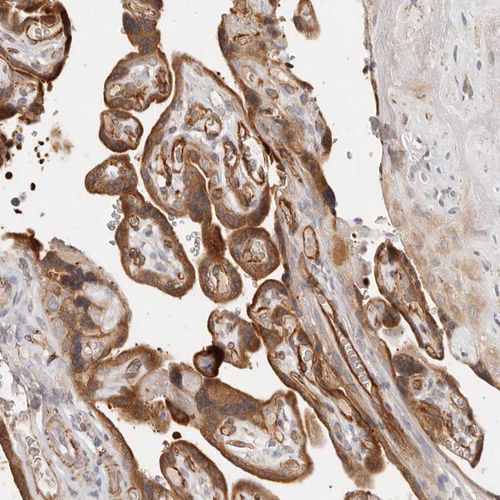

Immunohistochemical staining of human duodenum shows strong granular cytoplasmic positivity in glandular cells.